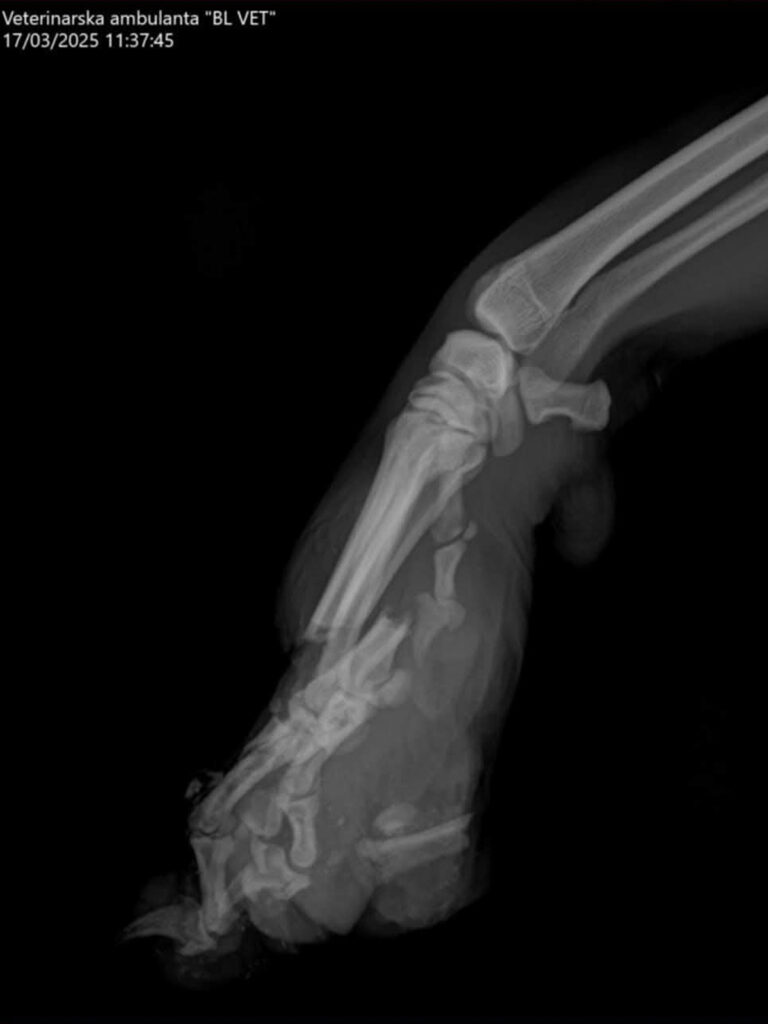

Bark war ein bosnischer Streuner, der von der ganzen Nachbarschaft geduldet und sogar gefüttert wurde. Dann kam er eines Tages so an die Tür. Niemand weiß, was passiert ist, aber da die Bahn gleich gegenüber ist, denken wir, dass er von einem Zug erfasst und schwer verletzt wurde. Die grausamsten Bilder ersparen wir euch. 😮‍💨